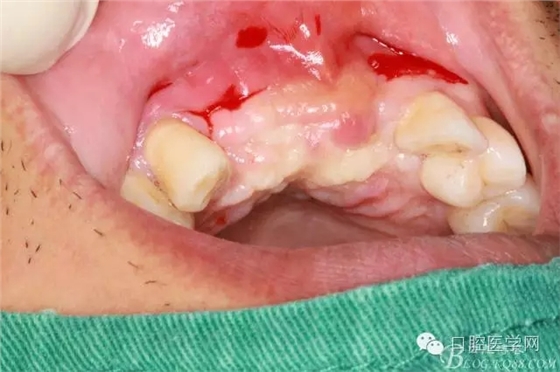

植入種植體左側(cè)3510,右側(cè)4010,植骨Bioss,蓋膜Cytoplast。骨膜減張垂直褥式縫合加間斷縫合。

遺憾沒有保留術(shù)前口內(nèi)照片,只有術(shù)后的。

之所以選擇Bioss是考慮其降解速度較慢,種植體接觸大面積為自體骨,Bioss可以很穩(wěn)定的緩慢吸收逐步引導(dǎo)骨再生。

后期的修復(fù)工作由之前的轉(zhuǎn)診醫(yī)生后續(xù)處理,由于GBR過程骨膜減張導(dǎo)致角化牙齦不足3mm,建議角化牙齦移植改變其更好的牙齦生物型。